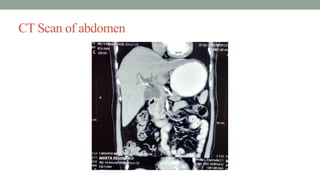

CT scan of abdomen

CT Scan of abdomen:

CT scan ofabdomen

CT Scan ofabdomen:

Confirmatory diagnosis: • Obstructivejaundice due to carcinoma of head of the pancreas.